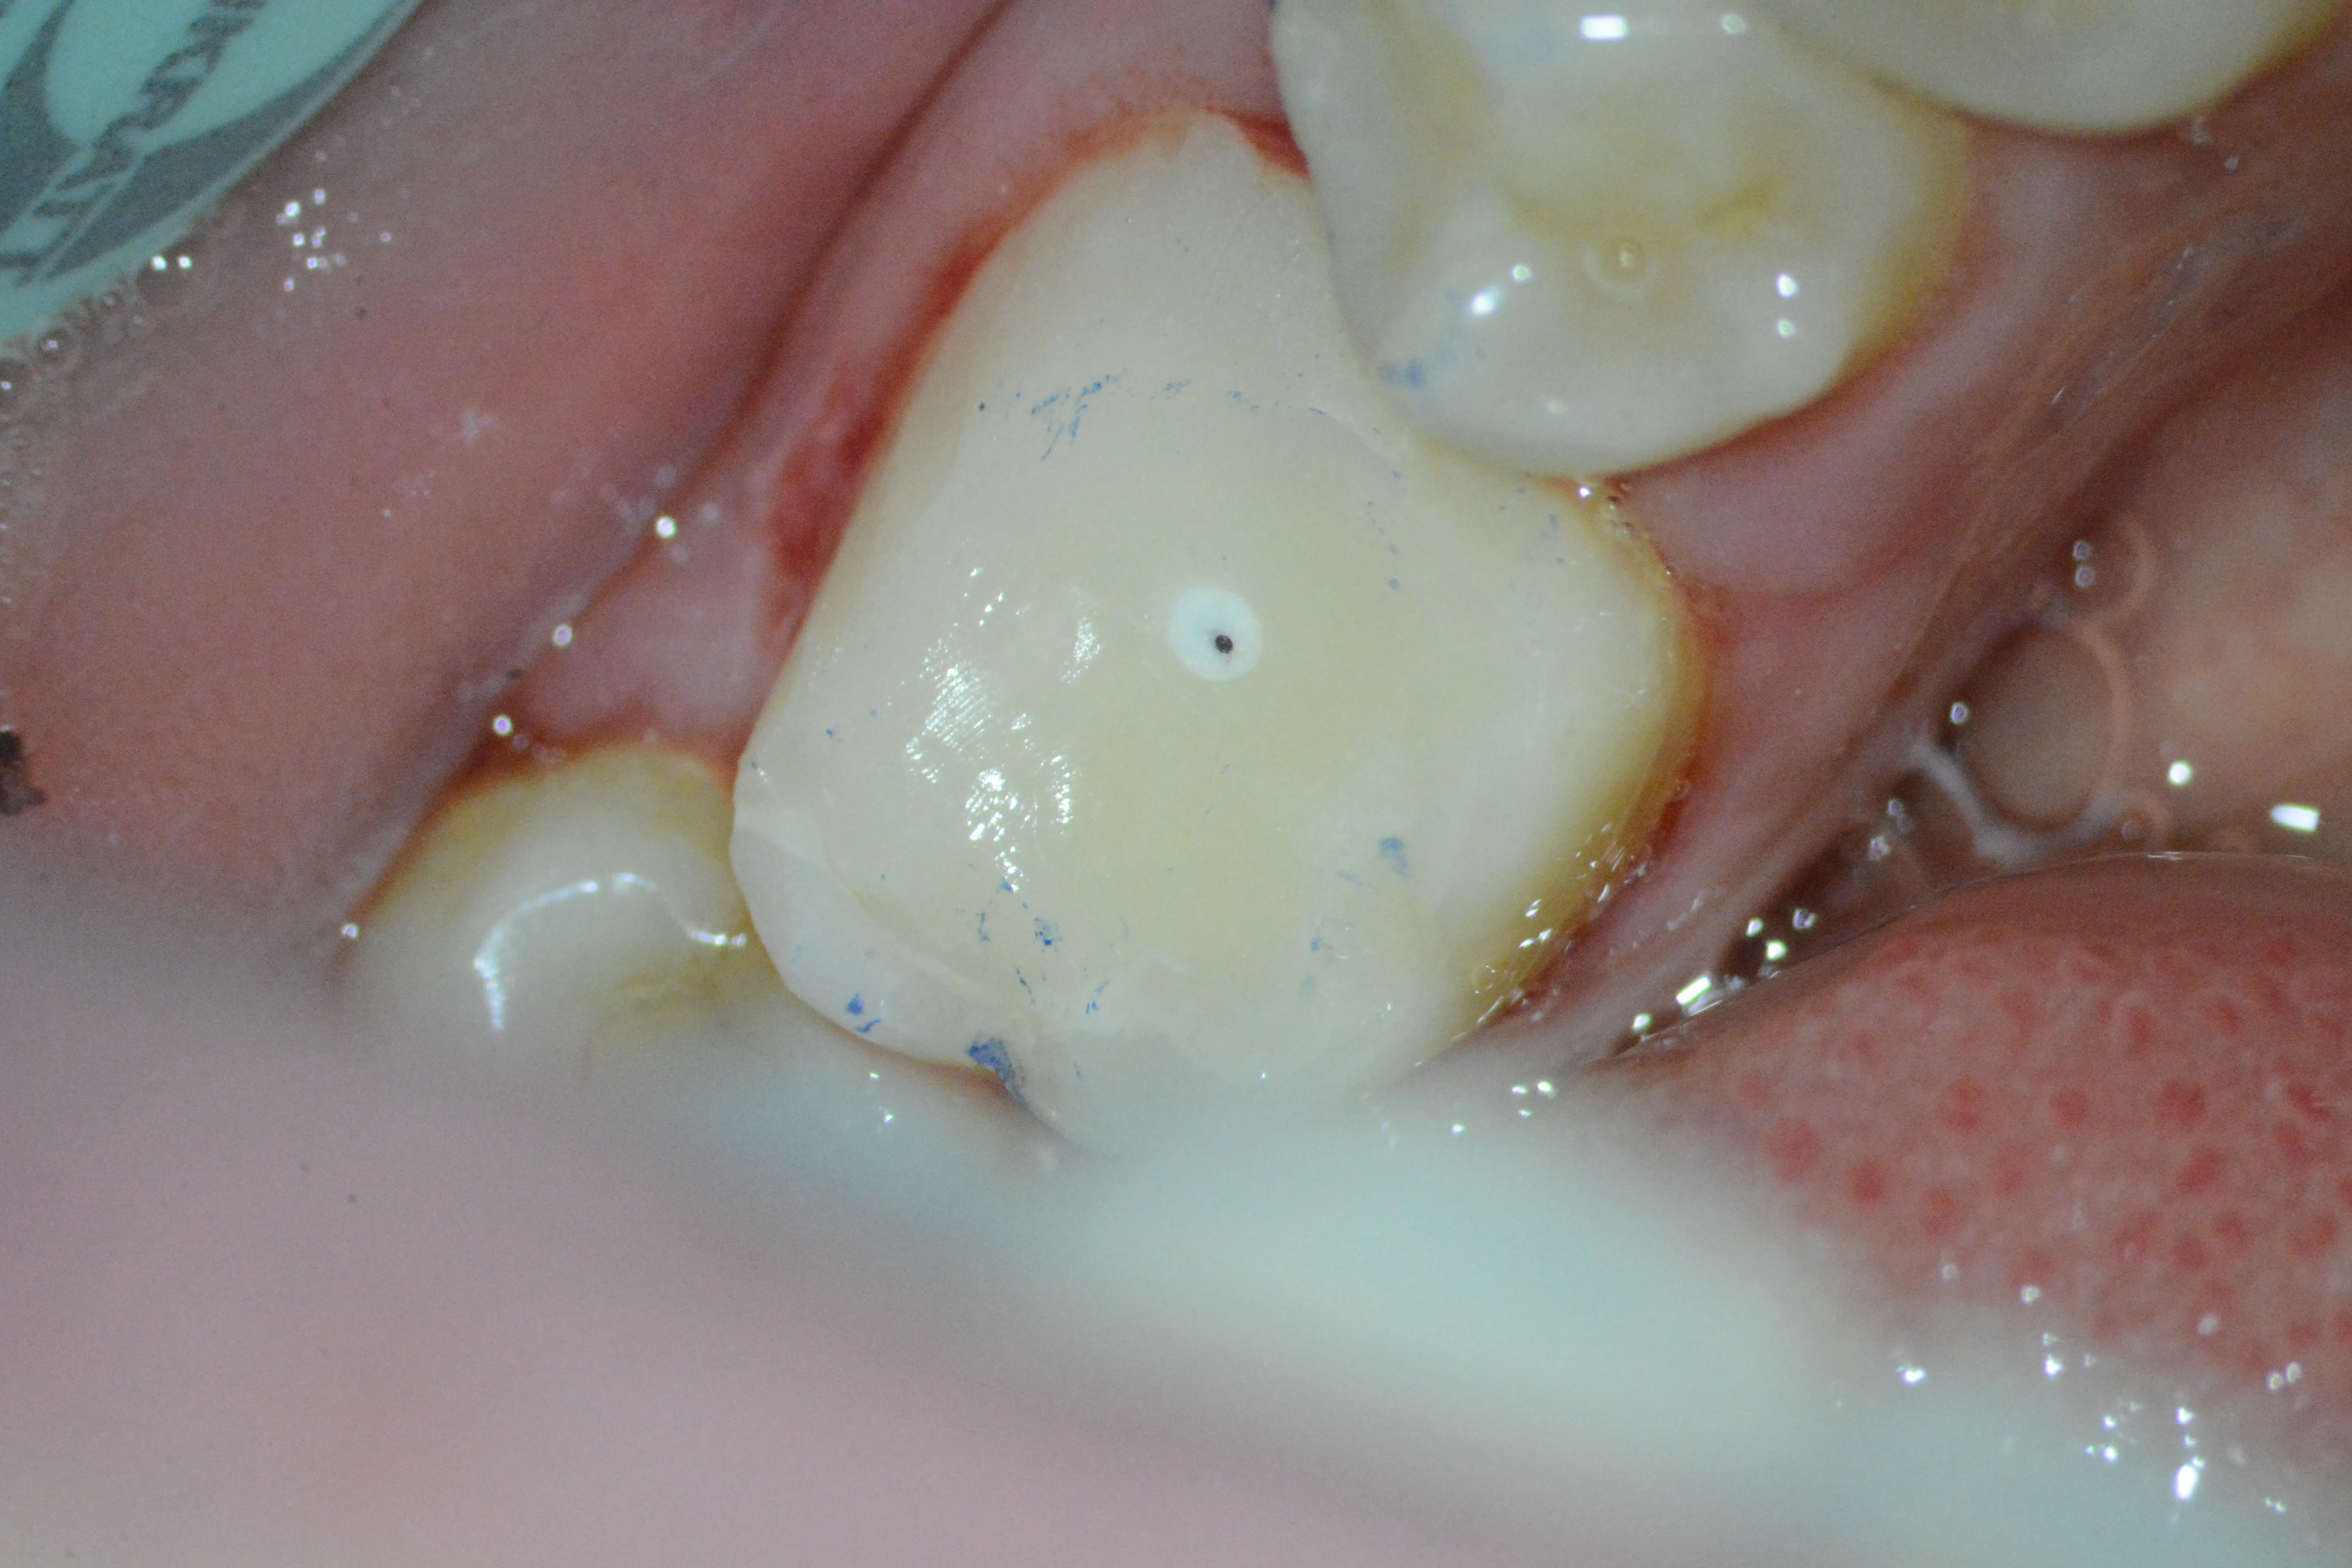

2 – Aspect clinic inițial